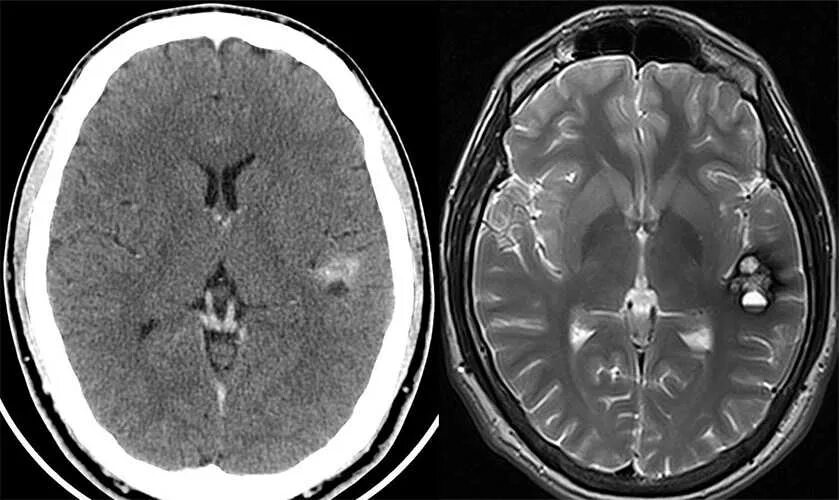

Чем отличается кт от мрт головы